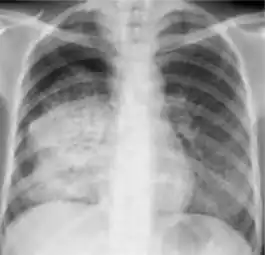

-

Chest x-ray showing nodule with margins that are indistinct or poorly defined (tree-in-bud sign) in post-primary pulmonary TB.